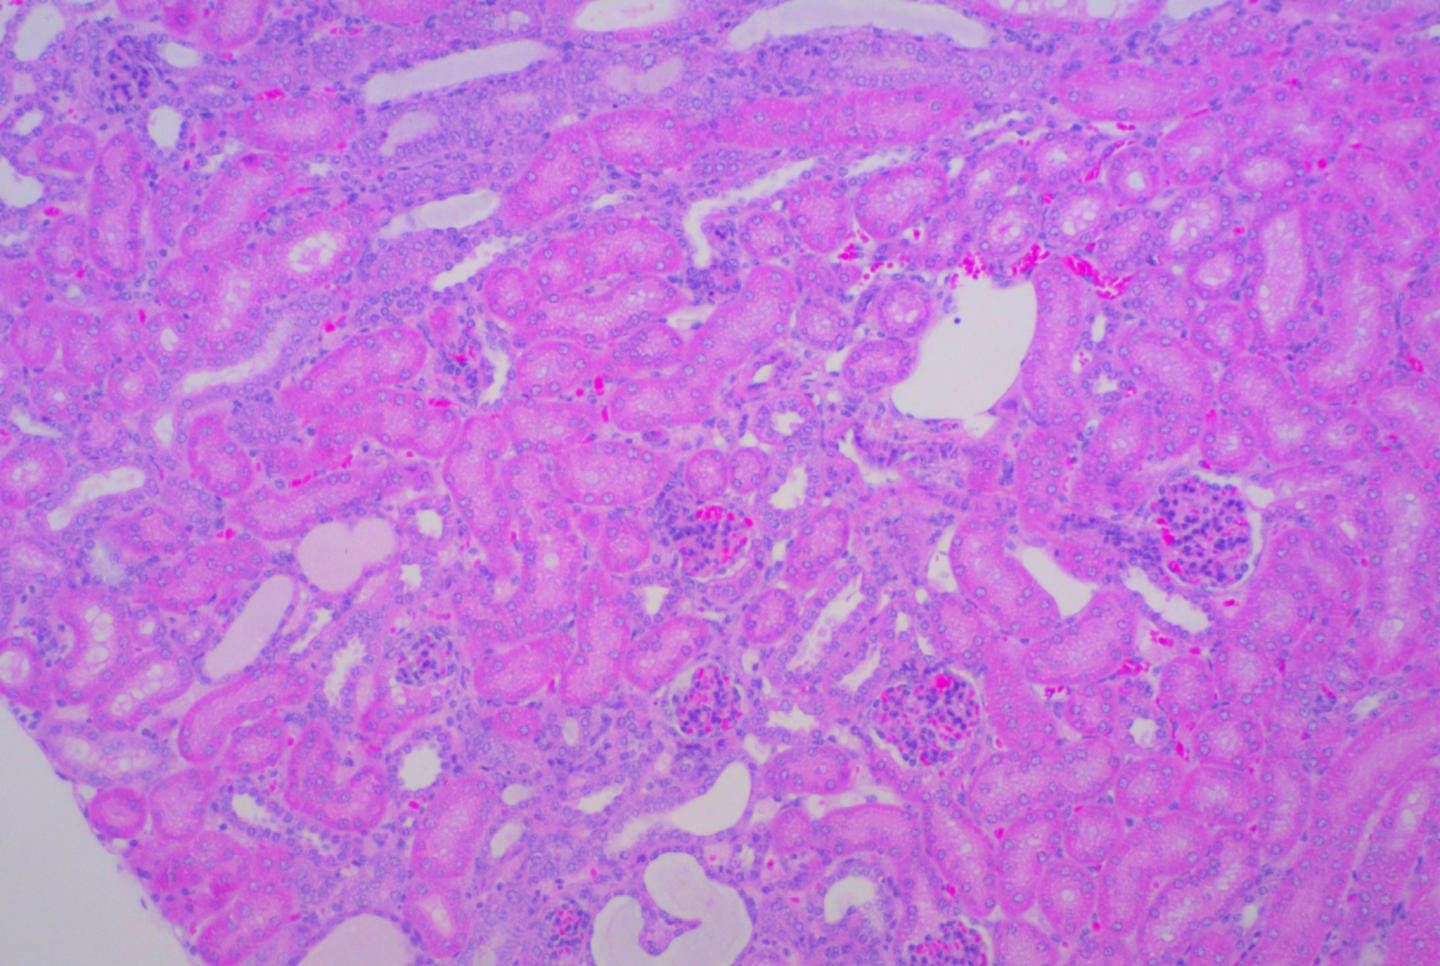

Renal fibrosis or the scarring of kidneys, following an injury, reduces their function and can cause kidney disease to progressively worsen. In a recent study, published in Kidney International , researchers from Duke-NUS Medical School (Duke-NUS) in Singapore and Duke University have shown that drugs that target Wnt secretion by inhibiting Porcupine, a protein usually targeted for cancer treatment, may reduce renal fibrosis and protect the kidneys.

In the study, one ureter, the tube from the kidney to the bladder, was blocked so that the affected kidney became damaged and scarred. The team demonstrated that inhibiting Wnt secretion interrupted the dangerous build-up of scar tissue in the kidney. These findings suggest a novel therapeutic approach to protect the kidney from scarring and provide a compelling rationale to test the use of Wnt secretion inhibitors for the treatment of kidney fibrosis and other progressive scarring disorders.